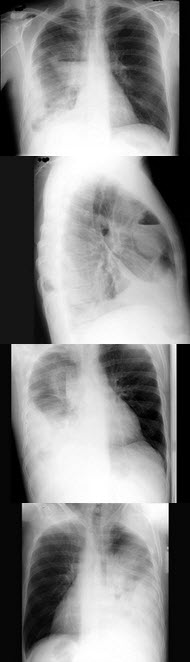

149、单项选择题

女,根据其正常足的影像图像,判断其最可能的年龄()

A.52岁左右

B.42岁左右

C.12岁左右

D.22岁左右

E.32岁左右

点击查看答案